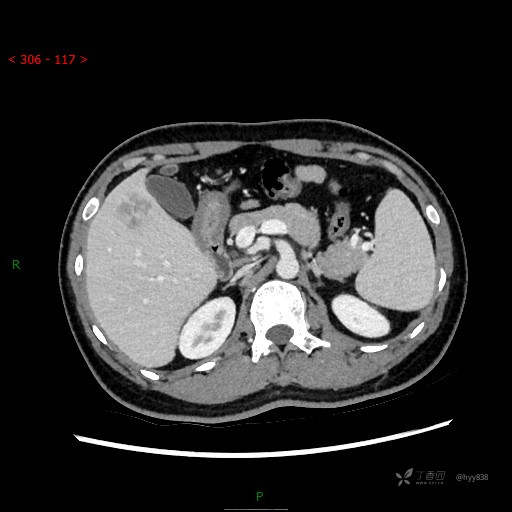

增强动脉期